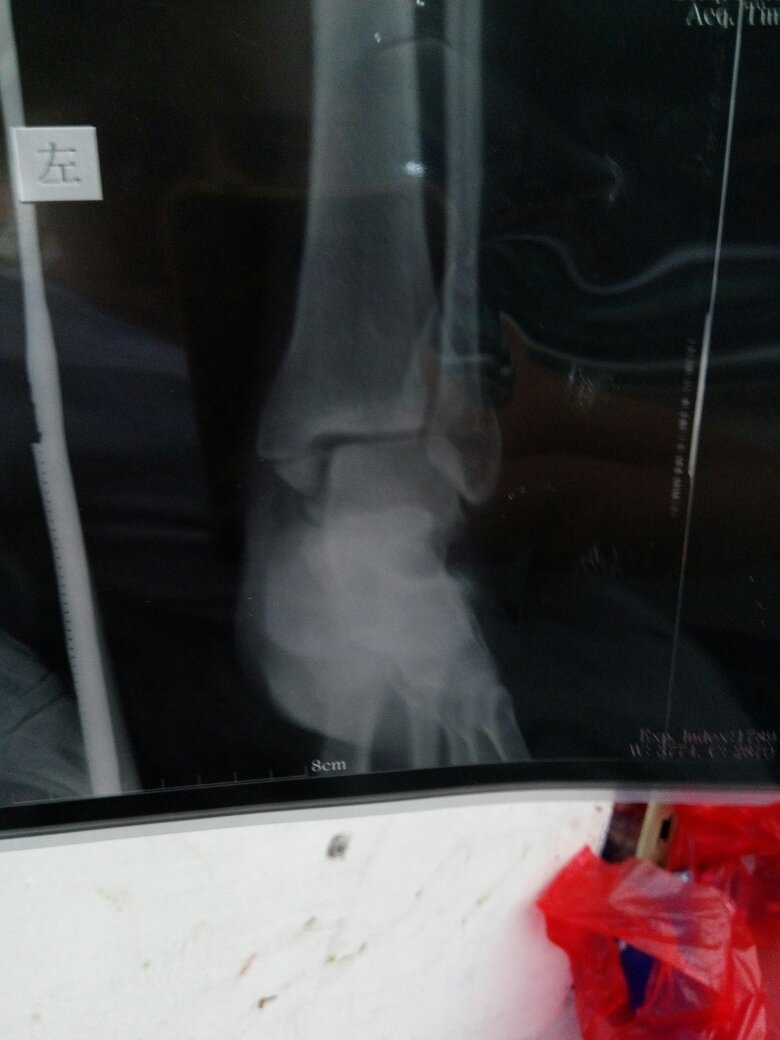

怀孕七个月了,左脚踝两边骨折石膏固定的,谁能帮我看看片子骨折严重吗 点击展开 133*****340_heC3 2016-09-22 13:41 满意回答 从片子上看,踝关节骨折确实比较严重,有错位。如果你没绣否糕有怀孕的话,笼貌肯定是需要朗脑立马做手术的。 匿名用户 2016-09-22 13:53 宝宝知道提示您:回答为网友贡献,仅供参考。 相关问题 脚踝处轻微骨折如果用石膏固定要固定多久 骨折后要拆石膏了,只是轻度骨折,可是脚踝? 骨折后要拆石膏了,只是轻度骨折,可是脚踝?